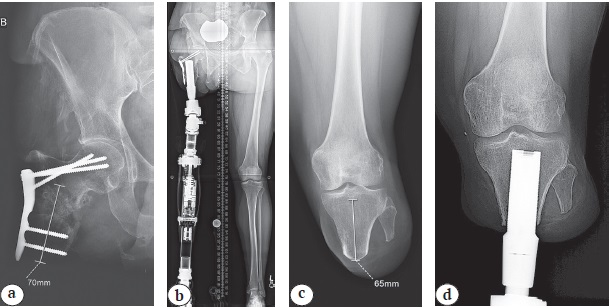

Figure 1. Osseointegrated Prosthetic Limb (OPL) used in the majority of articles reviewed in this manuscript:

a[*] — exploded view with the componentry arranged at approximately the proximal-distal levels, in which they would reside after being assembled and implanted in a patient who had undergone a femoral amputation (1 — proximal cap screw; 2 — OPL body; 3 — safety screw; 4 — dual cone abutment adapter; 5 — taper base screw; 6 — proximal connector; 7 — prosthetic connector. Components 6 and 7 are one of various styles of mating the dual cone (4) with a prosthetic terminal device);

b — long-standing X-ray of a patient with right transfemoral amputation in the socket prosthesis, identifying the valgus hip position seen in many socket users;

c — long-standing X-ray of the same patient after transfemoral osseointegration, showing the anatomic alignment of the leg;

d — close-up photograph of the transcutaneous portal for the prosthesis. Note the stable skin-implant interface